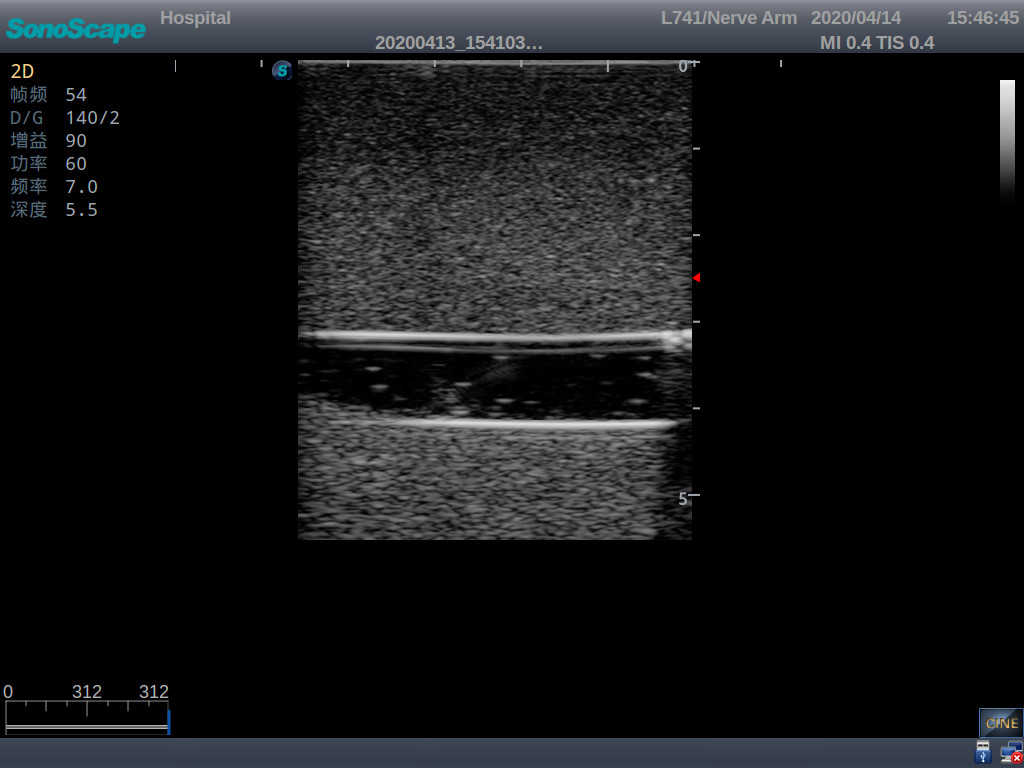

Model TYE1510.1

Product size(mm) 700×500×160

It is a model covering up from lobulus auriculae plane to the umbilical plane, and it has anatomical structures like clavicle, rib, sternocleidomastoid, jugular vein and basilic vein.

1)   Made of high molecular polymer ultrasound material, close to the real skin

2)   It can be used by real ultrasound machines

3)   Clear and real images of the tissues and organs (basilic vein and superior vena cava)

4)   When conducting vascular puncture, the piercing can be truly felt, and venous blood outflow can be seen

5)   Observe the guide wire marches

6)   Detect whether the catheter is properly placed